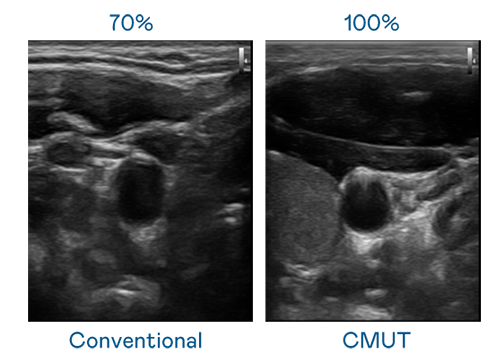

CMUT 技术是一种用电容式微机电元件来产生超音波讯号的技术。与传统 PZT 压电式技术相比,CMUT 频宽增加 30%,更宽频的超音波讯号让影像解析度大幅提升,是实现高影像品质医疗超音波扫描、促进精准医疗发展的关键技术。

超音波影像的解析度高低,首先取决于探头能发出的讯号频宽。j9九游会首页登录 CMUT 可提供高清晰的超音波讯号,提供高频宽、高灵敏度、影像纹理细节更高的超音波影像,协助医护人员缩短影像判读时间及利用精准的医疗影像进行诊断。